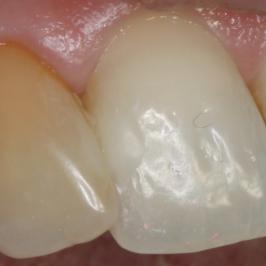

Discoloration due à un traitement de racine

Après 1 mois et 2 séances de blanchiment interne